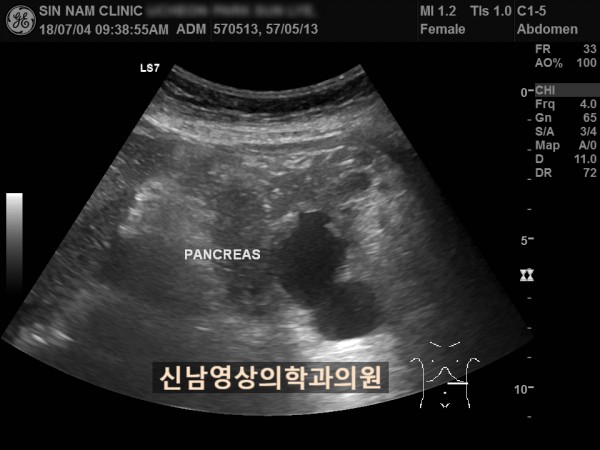

아래 환자분은 60대 여성분으로 식사만 하면 복통이 나타나서 내과에서 위 / 대장 내시경을 받으셨지만 정상으로 진단받았던 분으로 내과에서 복부 초음파검사를 했지만 이상 소견을 발견하지 못했던 분입니다.

복부 초음파 검사상 췌장꼬리(미부)에서 발생한 암으로 대장 장간막으로 전이가 되어서 대장내시경에서는 정상으로 확인되었고, 식사를 하면 장간막 전이때문에 장폐색 증상으로 복통이 발생하셨던 것으로 복막으로 전이가 진행되어 복수까지 있었습니다.

초음파 검사는 검사를 진행하는 사람의 숙련도에 따라 진단의 정확도가 결정되므로 영상의학과 전문의가 진료하는 병원에서 초음파 검사를 받아보실 것을 권합니다.

상복부 초음파 검사는 초음파를 생성하는 탐촉자를 상복부에 대고 초음파를 보낸 다음 되돌아오는 초음파를 실시간 영상화하는 검사입니다.